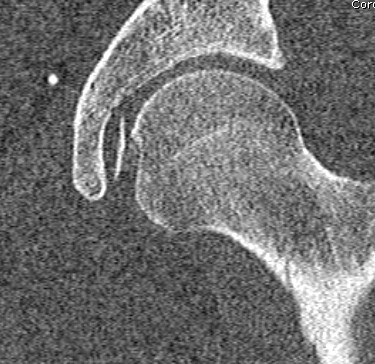

Anatomy

Inherently stable joint

- large head on smaller neck

- allows deep seating of femoral head

- acetabulum deepened by labrum

- capsule reinforced by ilio/pubo/ischio femoral ligaments

40% femoral head in contact with articular cartilage

10% in contact with labrum

Blood supply

Majority by deep branch of Medial Circumflex Femoral Artery

- minimal by medial epiphyseal artery via ligamentum teres

- little to non via LCFA

MCFA

- arises medial aspect of profunda

- along posterior intertrochanteric crest extracapsular / back of femoral neck

- passes between iliopsoas and pectineus medially

- runs along inferior border of obturator externus, above adductor brevis

- deep to quadratus femoris

- emerges between quadratus and inferior gemellus

- runs over conjoint tendon (2 gemelli and obturator internus)

- then penetrates capsule between conjoint and piriformis

- runs along superior aspect of neck to femoral head

Transverse branch (to ischium) and ascending branch (to trochanteric fossa0

- arise anterior to quadratus

Must protect this deep branch MCFA in a posterior approach

With dislocation and capsular tears

- some ascending cervical branches stretched/kinked

- emergent reduction can improve blood flow to femoral head